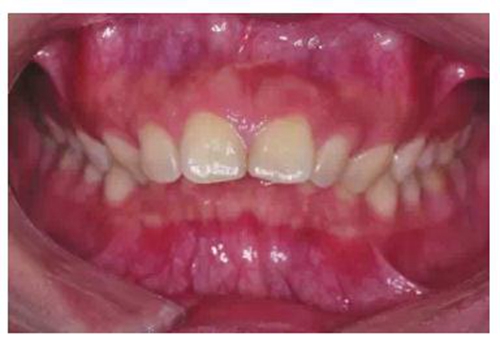

由于有很多患者在微笑時“頰廊”會比較明顯(圖2),這種情況往往預(yù)示著其上牙弓狹窄或上頜后牙過于舌傾(圖3),從而影響了微笑的美觀,正畸時有必要直立上頜后牙,這樣就可以創(chuàng)造飽滿的微笑,這類病例可以考慮選擇上頜前磨牙的零度轉(zhuǎn)矩,有效實現(xiàn)上頜后牙的直立。

圖2 患者在微笑時“頰廊”

圖3 存在“頰廊”者的口內(nèi)情況